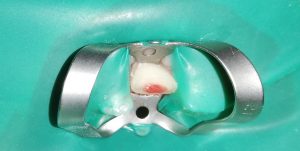

We at the Department of Pediatric & Preventive Dentistry focus on comprehensive oral health care needs of a child from infancy to adulthood and provide comprehensive, therapeutic as well as preventive care to all children including those with special care needs.

- E-Book published on Restorative materials in Pediatric Dentistry (Lambert Academic Publishing) on 11th June 2025.